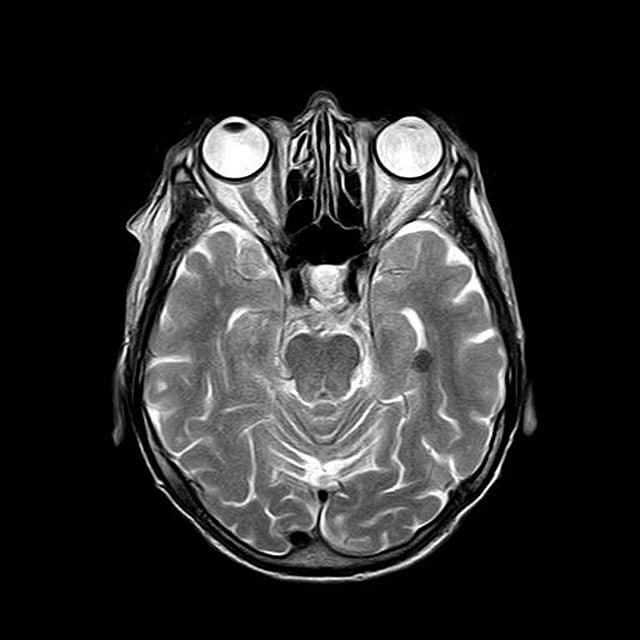

패쇄공포증 때문에 MRI 검사가 두려우신가요? 진정제 사용부터 개방형 MRI까지, 안전하고 편안한 MRI 검사 방법을 자세히 알려드립니다. 의료진과 상담하여 최적의 방법을 찾아보세요.

패쇄공포증은 많은 분들이 겪는 불안장애 중 하나로, 특히 MRI 검사 시 큰 스트레스를 유발할 수 있습니다. 좁은 공간에 들어가야 하는 자기공명영상 촬영은 밀폐공포증 환자들에게 큰 도전이 됩니다. 하지만 다행히도 현대 의학에서는 이런 분들을 위한 다양한 해결방법들이 마련되어 있습니다.

패쇄공포증은 좁거나 닫힌 공간에 있을 때 극도의 불안감과 공포를 느끼는 정신건강 상태입니다. MRI실의 좁은 터널 구조는 이런 증상을 더욱 악화시킬 수 있어 환자안전과 검사품질에 영향을 미칠 수 있습니다.